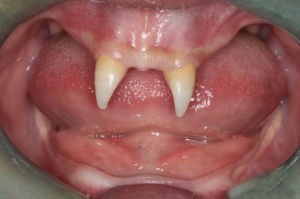

3、缺牙或牙發育不良。

有汗腺、毛髮、甲板異常,錐形牙齒對本症診斷甚有幫助,加上汗腺功能檢查,必要時皮膚活檢可明確診斷。

先天性外胚層發育不良綜合徵系外胚層發育不良所致,故無根治療法亦無特殊治療。對閉汗型,尤其是嬰幼兒患者,在夏季發病的時候需要給予涼爽環境,遇有發熱可用冷毛巾冷敷或以涼水沖洗,幫助散熱、降溫。同時也要預防高熱驚厥、傳染病、呼吸道感染等。若出現牙齒缺損的症狀可裝義齒,有助於咀嚼和說話;若出現皮膚乾燥、局部表皮缺如或附屬檔案缺損等症狀,應儘量避免不良刺激與外傷,並注意預防感染。

典型病例

先天性外胚層發育不良綜合徵